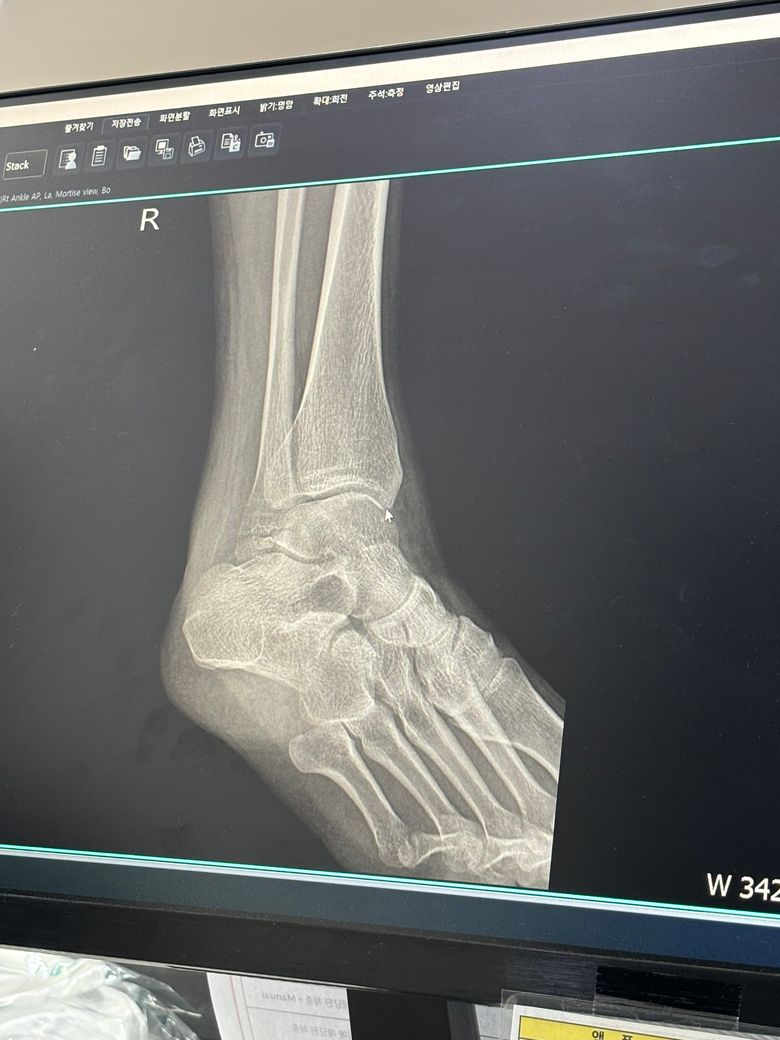

우측 외복사골 골절 수술 비수술 여부 궁금합니다

넘어져서 우측 외복사골이 골절되었습니다 엑스레이 첨부 합니다 ㅜㅜ 해당부위는 많이 움직이는 부위여서 수술을 해야한다고 하시는데 대학병원 파업중이라 개인병원에서만 진단 받아봐서 비수술도 가능할지 여쭤봅니다

• 1번 째 사진

외복사골 골절은 뼈의 어긋남 정도와 관절면 손상 여부에 따라 수술 여부가 결정됩니다. 엑스레이상 골절부위가 벌어져 있거나 관절면까지 영향을 주면 수술이 권장됩니다. 미세 골절이거나 정렬이 잘 유지되면 비수술적 치료도 가능합니다 정확한 판단인 정밀 진단을 받는 것이 필요하고 전문 병원을 방문하시는 것이 좋아요!